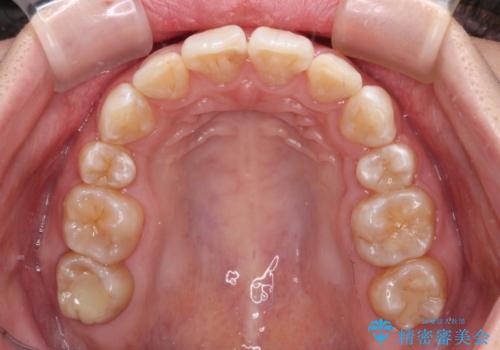

- 矯正装置

- 審美装置

- 治療計画

- 口元の閉じにくさと、前歯のでこぼこの歯並びを気にして来院された患者様です。

口元を積極的に引っ込めるために、上下左右の小臼歯計4本を抜歯することとしました。

咬み合わせが深く、咬合力強いため、補助装置を使用しながら積極的に口元を下げることとしました。

矯正治療終了近くに九州へ引っ越すことになってしまい、なかなか来院することができなくなったため、引っ越してから1年以上の期間が必要となってしまいました。